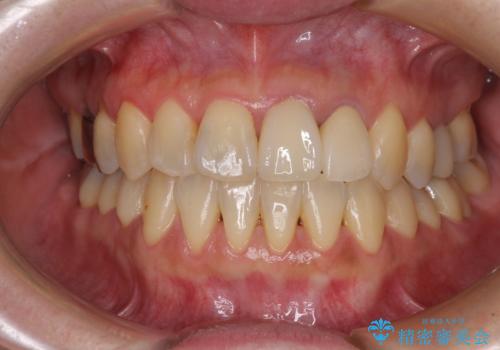

[MTMを行い歯の神経を保存] 歯周補綴ブリッジ